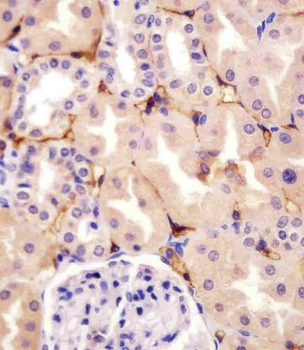

IHC staining of FFPE human colon carcinoma with CD73 antibody (clone NT5E/2545). HIER: boil tissue sections in pH9 10mM Tris with 1mM EDTA for 10-20 min and allow to cool before testing.